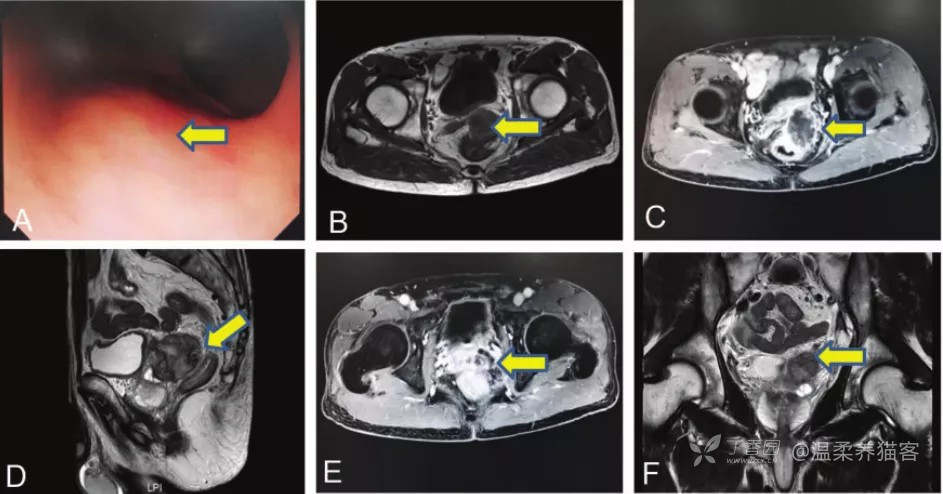

病例二

图片来源:Li W, et al. Journal of International Medical Research, 2022, 50(6): 030006

一例直肠 DDL,68 岁,男,因下腹部间歇性绞痛 6 个月,体重减轻 5 公斤就诊

(A) 肿瘤结肠镜检查图像;(B) 轴面 T1WI;(C) 轴面 T1 增强;(D) 矢状面 T2WI;(E)轴面增强 MRI 显示左侧精囊受累;(F) 冠状面增强 MRI 显示左侧精囊受累